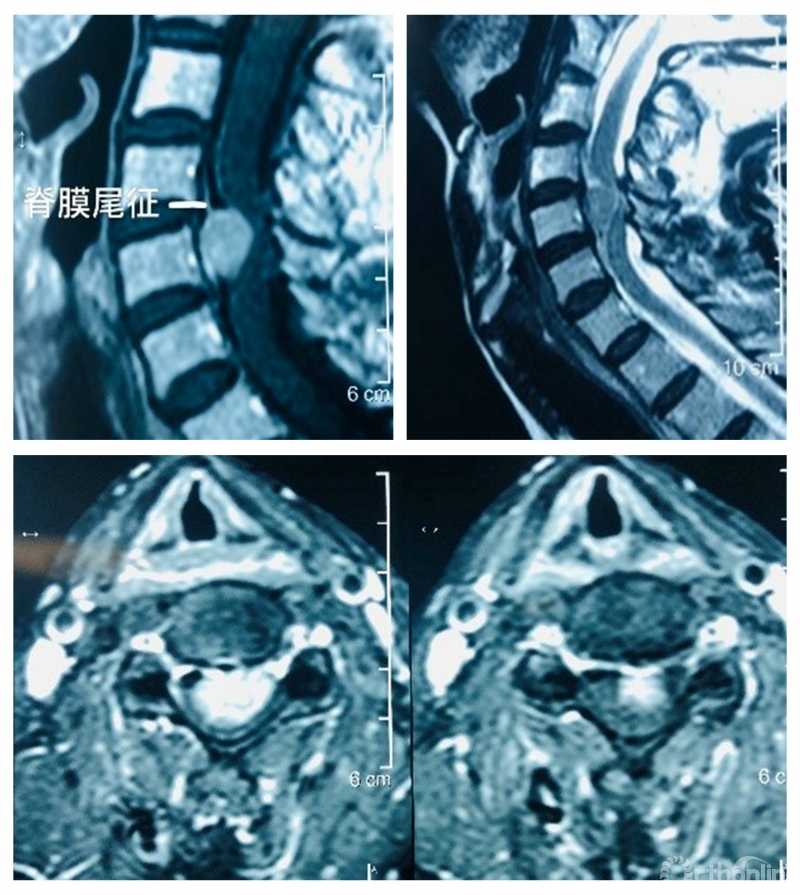

核磁共振显示:第5颈椎后部椎管内硬膜下脊髓腹侧脊膜瘤伴脊髓压迫。脊膜尾征明显。肿瘤最大侵占椎管达90%。术前横断面增强核磁共振显示肿瘤高度压迫脊髓。

术前影像学检查